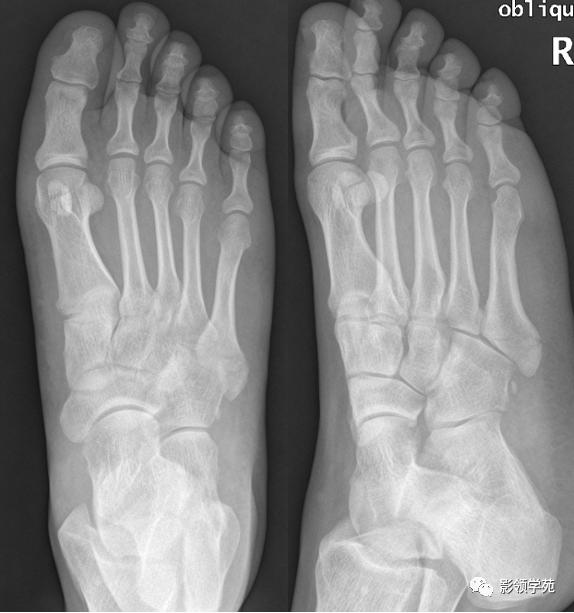

case2

男 26岁 外伤,X线诊断第5跖骨基底部骨折,未排右足骰骨撕脱骨折

第五跖骨粗隆

第五跖骨基底部骨折,常为横行骨折,即骨折线垂直于跖骨骨干,它是由于腓侧短肌肌腱应力所引起的撕脱骨折,也称“JONES骨折”。该骨折应与第五跖骨粗隆突起鉴别,尤其是9-15岁的儿童,常常可以出现第五跖骨基底部的骨骺,常表现为纵行透亮线,骨片边缘一般规则光滑,周围软组织无明显肿胀。

第五跖骨粗隆存在独立的骨化中心,并且可有一个或多个骨化中心,常见于10~15岁儿童。一般25岁左右与第五跖骨其余部分融合。

我们所常见的第五跖骨基底部骨折的骨折线一般都是垂直于长轴的,平行于第五跖骨长轴的骨折非常罕见。从外力方向、方式来发现,很难使第五跖骨基底部发生纵形骨折,而该处确实存在骨骺,大量的误诊就是把骨骺当骨折。